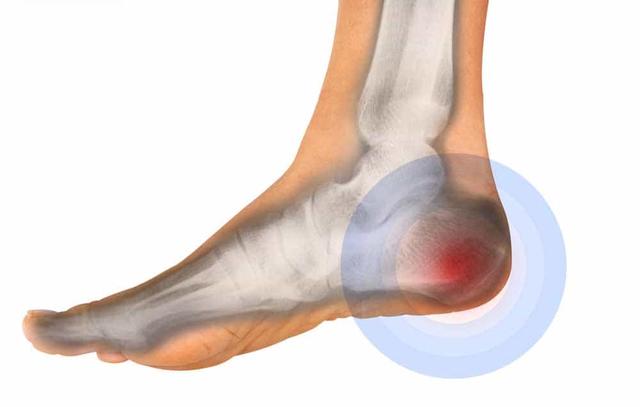

在早上起来不敢下地,落地那一脚就感觉有无数根钢针在扎自己的脚后跟,这种情况主要是由足底筋膜炎或跟腱炎.引起的。归根结底,劳损发生在肌腱和骨骼相连的部分。不过这个问题虽然不大,但是治疗起来还是比较麻烦的。民间有很多不同的措施,比如用花椒水泡脚,啤酒瓶子按摩足底甚至跺脚!那么,这些措施真的能帮助我们缓解脚后跟疼痛吗?会不会造成问题?我们今天聊聊吧。

有些患者有特殊的经典症状,如上下楼梯时脚后跟疼痛,例如在晨起的时候不敢落地,但走了一会儿,恢复了一会儿,症状又消失了,但休息一会儿又站起来时,这种症状反复出现,许多患者深受其扰。